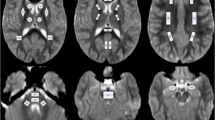

The raw magnitude and phase images from the 3D-FLASH sequence were transferred to an offline workstation, and quantitative susceptibility maps were reconstructed using the morphology-enabled dipole inversion (MEDI + 0) – method with referencing of the parenchymal susceptibility values to the intraventricular cerebrospinal fluid susceptibility [20, 21]. This method is a stepwise procedure including a total field estimation by a nonlinear fit of the multi-echo data, local field computation by spatial field unwrapping, and background field removal using the projection onto dipole fields algorithm (PDF) followed by inversion of this result in order to get the susceptibility map. The MEDI + 0 – method uses magnitude image-based priors (edges) during the numerical inversion process as well as a regularization term leading to a uniform susceptibility distribution of CSF in order to enhance the QSM image quality (as it was also described in [5]). R2* calculation is based on the auto-regression on linear operations (ARLO) method [22], which is included in the same toolbox as the MEDI + 0 method, provided by the Cornell MRI Research Lab, Cornell University, USA (http://pre.weill.cornell.edu/mri/pages/qsm.html). Region of interest spheres with a radius of 3 mm were manually placed by two neuroradiologists individually (PR, MPW; with more than 15 years of neuroradiological experience) in the right putamen (PT), head of caudate nucleus (CN), and globus pallidus (GP) using MRIcro (Chris Rorden; www.mricro.com) and its multiplanar visualization function. The GP ROI was placed anteriorly and covered both the internal and external parts of this nucleus (Fig. 1). We analyzed exclusively the deep nuclei on the right in order to prevent possible effects of hemispheric differences with higher iron levels in left-sided deep nuclei, which were described in adults and were attributed possibly to motor lateralization [23]. Susceptibility and R2* values within the ROIs were extracted using FSL [24]; mean QSM and R2* values were calculated using the two ROI datasets for each anatomical location. The software “IBM SPSS statistics” (SPSS: IBM Corp. Released 2019, IBM SPSS Statistics for Windows, Version 26.0, Armonk, NY: IBM Corp.) was used to assess the correlation (calculation of Pearson correlation coefficient R using a linear regression analysis) between age and susceptibility as well as R2* values of the three individual nuclei for the whole patient group. The Mann–Whitney U test was used to test for susceptibility differences between female and male children within each region and a multiple regression analysis was used to assess a possible influence of sex on the correlation between age and susceptibility values for each region. The p value requested was adapted to p < 0.005 due to the number of tests.

In very young children (grouped ages 0–12 months, n = 14), the quantitative susceptibility was very similar for the three deep grey matter structures with the highest susceptibility in the CN (mean ± SD: -8.2 ± 9.43 [all susceptibilities in ppb]) and the lowest in PT vs. GP (-29.4 ± 4.9 vs. -17.4 ± 5.7, respectively). The fastest susceptibility increase occurred within the GP, leading to a mean susceptibility value of 97.6 ± 39 in the 3 children older than 9 years (see Table 1 and Fig. 3). This is also represented by the highest slope of the correlation between age and susceptibility for GP (y = -32.28 + 1.15*x) as compared to the other two nuclei (CN: y = -13.38 + 0.3*x; PT: y = -30.33 + 0.23*x) (Fig. 3).